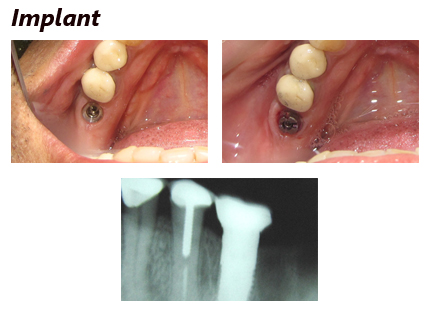

Dental implants.

Treatment Gallery